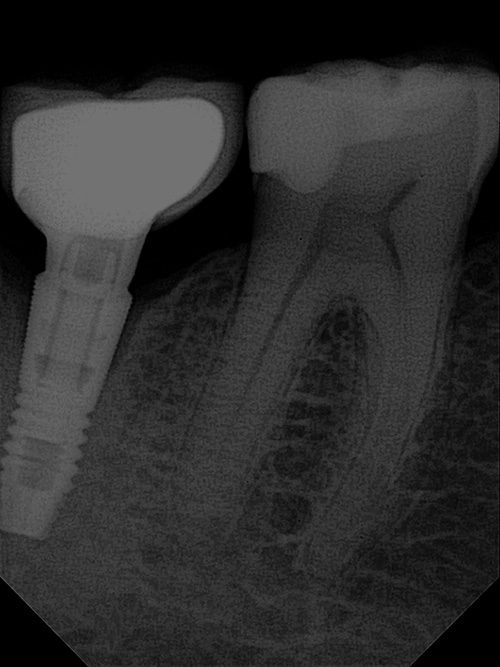

- Implantat- & Prothesenchirurgie: Optimierte Planung und Nachsorge.

OPTEO Sensor – Klinische Bildgalerie

Ultra-HD Bildqualität – 18,5 Mikron Präzision Außergewöhnlich klare und detaillierte intraorale Bildgebung.

Ein hochwertiger dentaler intraoraler Sensor

Ultra-HD-Bildqualität für perfekte Zahnfilme.

18,5 Mikron Auflösung.